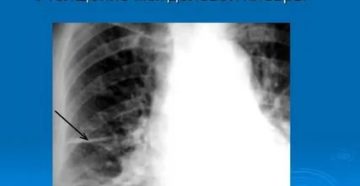

Уплотнение междолевой плевры справа что это || Уплотнение междолевой плевры справа что это Плеврит –…

Лечение уплотнения корней легких народными средствами Период межсезонья сопровождается затяжными дождями и простудными заболеваниями. В…